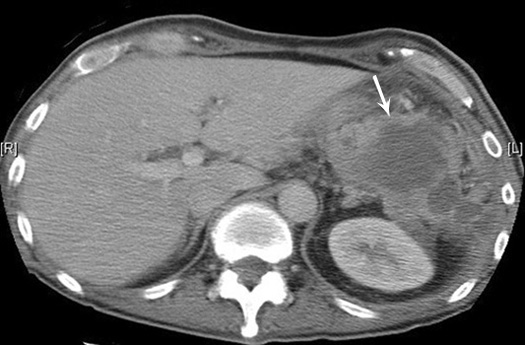

Subdiaphragmatic abscess post splenectomy

- Arrow points to multiloculated thick walled fluid collection in the left upper quadrant of the abdomen.

- Note absence of spleen.